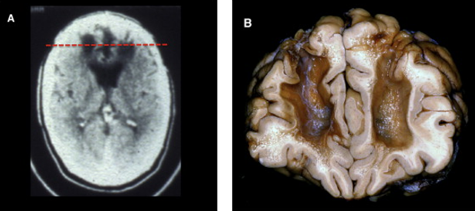

Prisonniers violents : Quels type de scan pour déterminer si pathologies plus prévalentes chez les incarcérés que dans la population générale ?

IRM et CAT